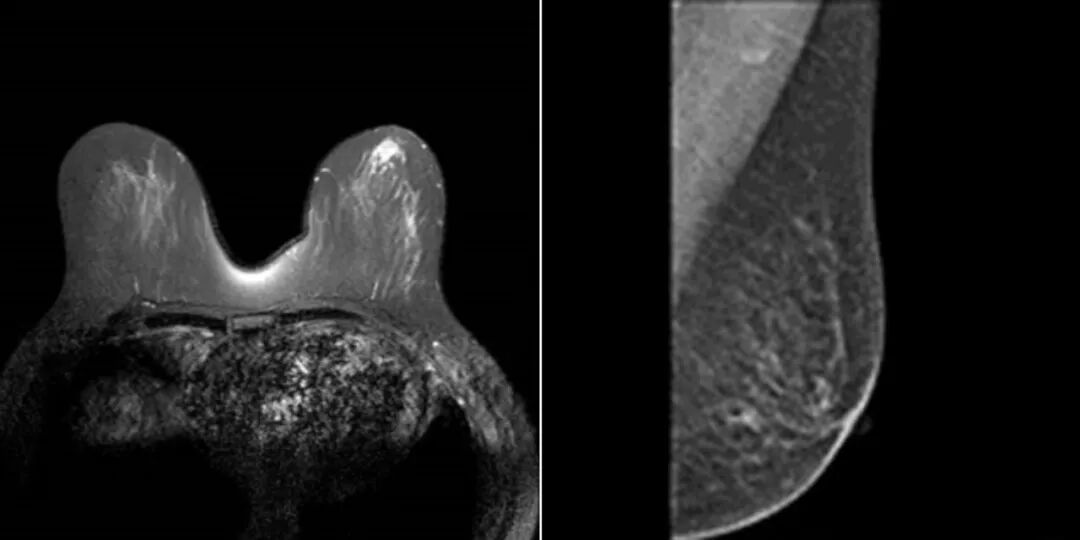

检查技术|乳腺癌各种影像学检查手段分析